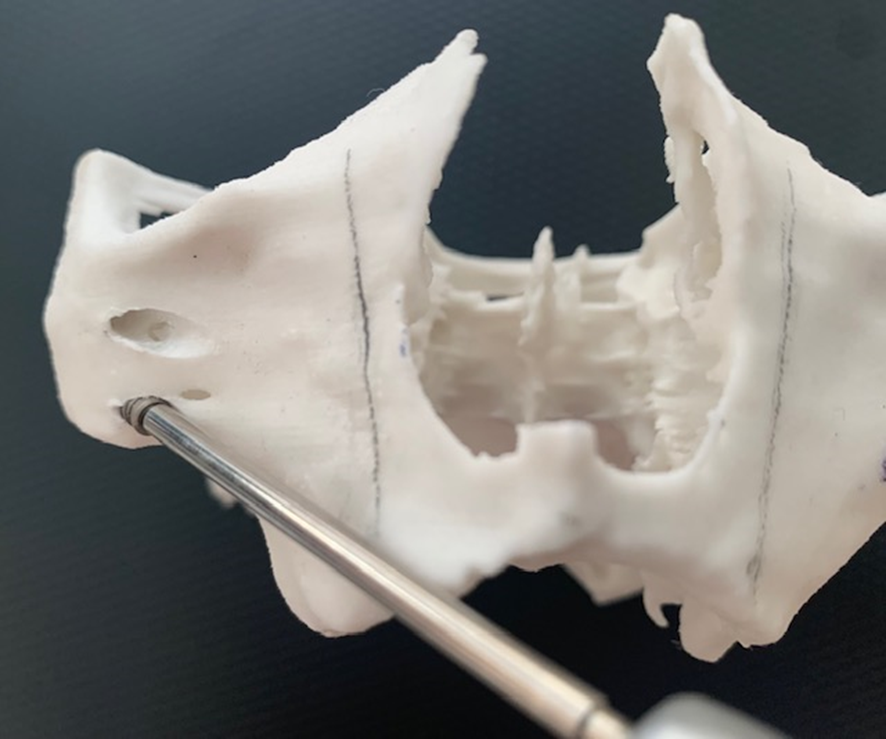

A montagem do Pilar Z exige do cirurgião-dentista habilidade e curva de aprendizado. Nem sempre se consegue adaptar o Pilar Z sem interferências ósseas. Por essa razão, adotamos uma rotina de instalação dos pilares na prototipagem, simulando assim, uma situação muito próxima do real no procedimento cirúrgico.

Desta forma, pode-se observar possíveis contatos ósseos no corpo da maxila ou do zigoma que não permitam o assentamento passivo do Pilar Z.

Conseguimos orientar a plataforma do Pilar Z através da chave de alinhamento, para assentamento passivo da prótese. A visualização do local de emersão do Pilar Z junto ao rebordo alveolar nos indicará onde realizar a osteotomia para confeccionar o “nicho” que abrigará a plataforma do mesmo.

Na simulação no biomodelo, os torques no parafuso do Cone Morse (15N) e na porca (20N) na junção entre o segmento B e C, deverão ser obtidos só para estabilizar o Pilar Z.

Importante que na montagem em boca, no torque da rosca que une os segmentos B e C (80 N), o parafuso fique 1/5 do seu diâmetro (aproximadamente 3 a 4 roscas), para dentro do tubo do segmento B.